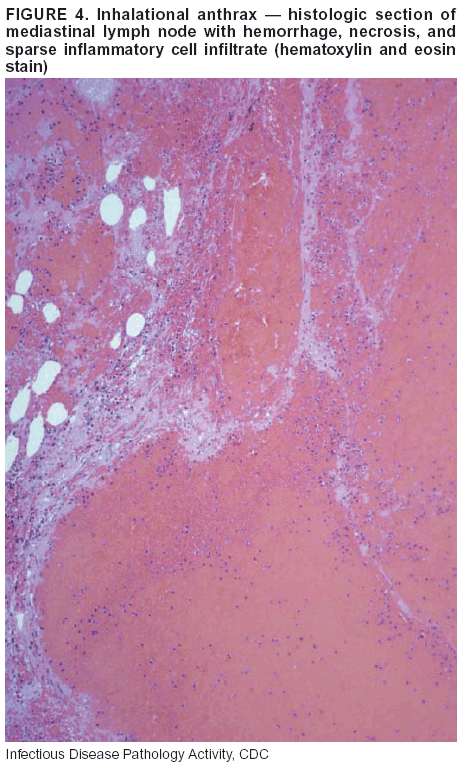

Pathologic Findings. Anthrax has three pathologic forms. Cutaneous anthrax is characterized by an eschar that forms where the bacteria entered the skin (Figure 2). Microscopically, the epidermis has necrosis and crusts, whereas the dermis demonstrates necrosis, edema, hemorrhage, perivascular inflammation, and vasculitis. The lymph nodes that drain the skin site eventually become enlarged, necrotic, and hemorrhagic. Gastrointestinal anthrax is distinguishable by hemorrhagic ulcers in the terminal ileum and caecum accompanied by mesenteric hemorrhagic lymphadenitis and peritonitis. Inhalational anthrax is characterized by hemorrhagic mediastinal lymphadenitis (Figure 3) accompanied by pleural effusions. Histologically, lymph nodes have abundant edema, hemorrhage, and necrosis with limited inflammatory infiltrate (Figure 4) (18,25--29). As any of the three anthrax forms progresses, the bacteria can spread to abdominal organs, producing petechial hemorrhages, and to the central nervous system, producing hemorrhagic meningitis (i.e., cardinal's cap) (Figure 5).

If possible, given the constraints of case volume and biosafety concerns, complete autopsies with histologic sampling of multiple organs should be performed in deaths potentially caused by infections with biologic terrorism agents. Autopsy diagnostic procedures for the Category A agents include microscopic examination, combined with the collection of specimens for additional tests that will aid in determining a definitive organism-specific diagnosis. Blood, cerebrospinal fluid, and tissue samples or swabs should be placed in transport media that will allow bacterial and viral isolation. Serum should be collected for serologic and biologic assays. Tissue samples should be frozen for polymerase chain reaction (PCR). Tissue samples should also be placed in electron microscopy fixative (glutaraldehyde). Microscopic examination of formalin-fixed, paraffin-embedded tissues stained with hematoxylin and eosin (H&E) is essential to characterizing the patterns of tissue damage defining a syndrome and establishes a list of possible microorganisms in the differential diagnosis. To enhance surveillance for these conditions, a matrix of potential pathology-based syndromes (Table 1) has been developed to guide autopsy pathologists in recognizing potential cases (24). Special stains (e.g., tissue Gram and silver impregnation stains [Steiner's or Warthin-Starry]), can be helpful in identifying bacterial agents. Additionally, specific immunohistochemical (IHC) and direct fluorescent assays (DFA) for the Category A terrorism agents have been developed and are available at CDC. These tests can be performed on formalin-fixed tissues. Clinical and pathologic characteristics of the Category A agents and corresponding diagnostic methods are summarized in this report (Tables 2 and 3).